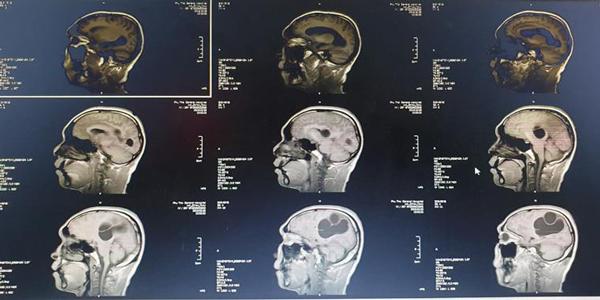

Hình ảnh chụp CT sọ não bệnh nhân.

Tại Bệnh viện Đa khoa tỉnh Phú Thọ, người bệnh được chỉ định chụp CT sọ não, kết quả cho thấy ổ sán não khổng lồ ở bán cầu trái và vùng thái dương đỉnh phải. Phù não đè đẩy đường giữa, ngay sau đó bệnh nhân được chỉ định can thiệp ngoại khoa cấp cứu vào lúc 23 giờ ngày 09/03.